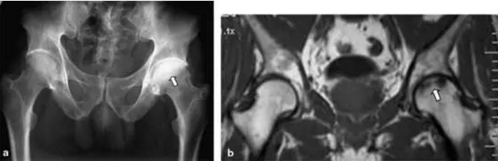

股骨头缺血坏死

轻度扁平至左股骨头的上方(空心箭头)表示第3期疾病。 右股骨头具有正常的轮廓,表明阶段2疾病。 黑色箭头表示修复区的边缘,代表死亡小梁上的新骨形成。 双侧的AVN,它通常发生在不同时间的每个髋部,并且疾病在每个髋部的分期可以,并且经常是,在不同的阶段。

骨盆的前后视图显示右股骨头的外侧部分因缺血坏死(箭头)扁平,相邻关节空间变窄,近关节硬化和代表退行性关节疾病的骨赘。